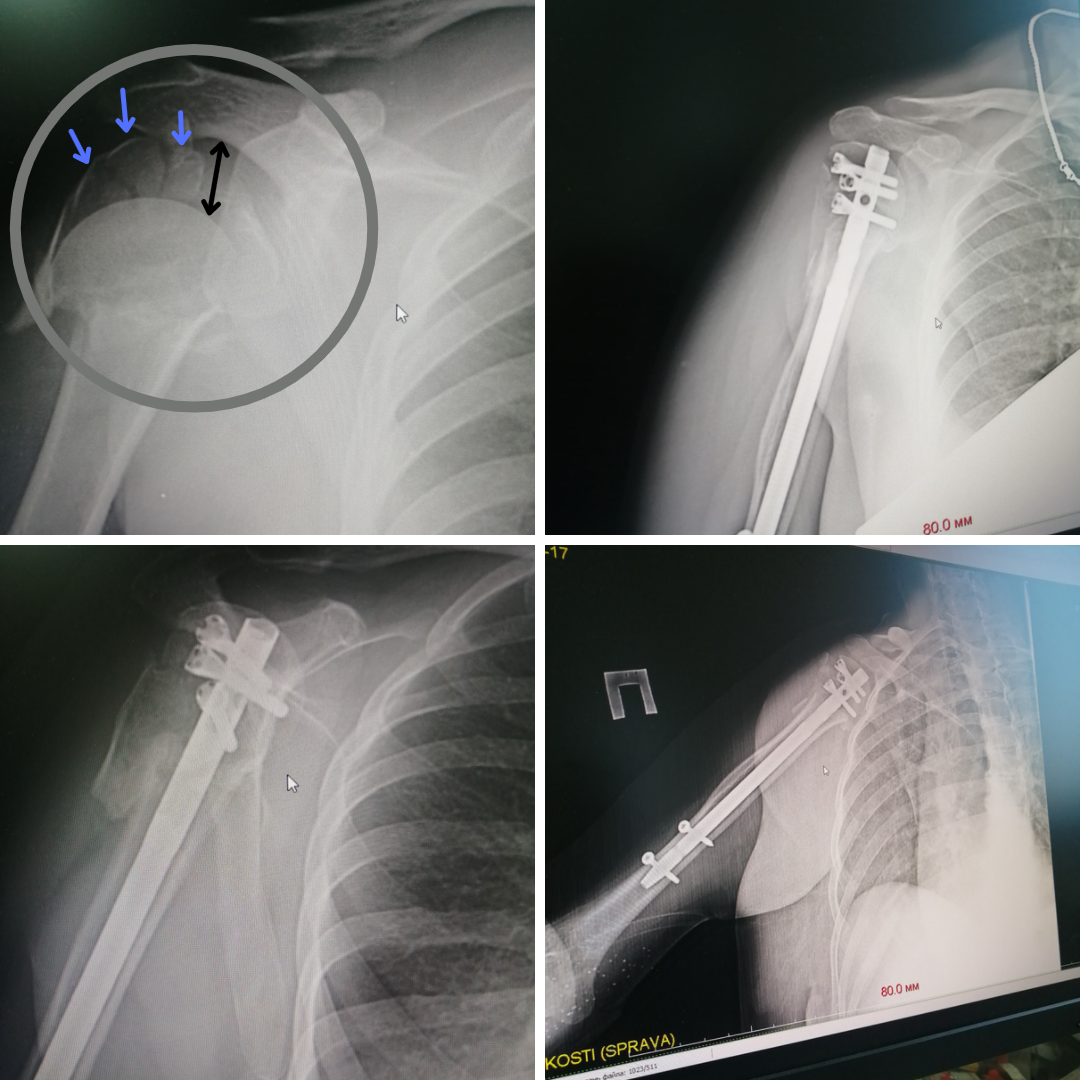

Одна из них серьёзно травмировала головку плеча. Мелкооскольчатый перелом стал настоящей катастрофой для сустава. Дома помощь ограничилась гипсовой иммобилизацией. Решив обратиться к сургутским травматологам, женщина преодолела не одну тысячу километров. При таких разрушениях, когда вероятность сращения незначительная, в качестве лечения, как правило, рассматривают эндопротезирование. Но, в отличие от коленных или тазобедренных суставов, установка и дальнейшая эксплуатация искусственного плечевого сустава сопровождается целым рядом сложностей и рисков. К тому же, нельзя было не принять во внимание возраст пациентки. Женщине чуть больше 40-ка, поэтому, хоть и в отдалённом будущем, но необходимость замены протеза всё-таки назреет. А перспектив повторного (ревизионного) эндопротезирования плечевого сустава немного.

– Было принципиально важно сохранить молодой женщине свой рабочий сустав. Оценив характер повреждений и современные возможности, мы выбрали метод интрамедуллярного остеосинтеза. Это внутрикостный вид оперативного лечения: в костномозговую полость погружается многофункциональный штифт-фиксатор, а затем винтами закрепляются образовавшиеся при переломе осколки. Технически операция довольно сложная, она требует чёткого предварительного планирования и тщательного обследования пациента. Однако травматичность такого вмешательства минимальная, конечность можно нагружать уже через несколько дней. Сейчас пациентка разрабатывает руку на занятиях ЛФК, функции конечности вернулись на 50%, перелом консолидировался, болевой синдром регрессировал, – говорит заведующий ортопедо-травматологическим отделением №4 Евгений Бойко.